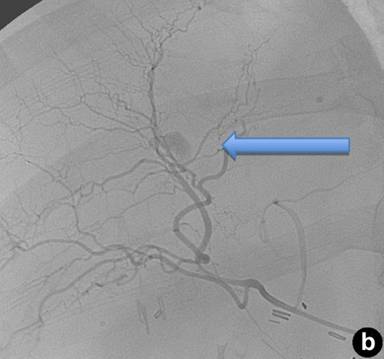

The patient returned three weeks later with near-syncopal symptoms, melena, and hematochezia. As the patient was exhibiting signs of intra-luminal bleeding, his first line diagnostic method was endoscopy which had to be repeated the following day due to clotted blood in the stomach. An additional 9 units of packed red blood cells were transfused. A tagged red-blood cell scan demonstrated bleeding localized to the proximal small bowel, and angiography demonstrated a right intra-hepatic artery pseudoaneurysm (Figure 2ab). The appearance of this pseudoaneurysm was small and intrahepatic and there was no extravasation of contrast or communication with the biliary tree. However, this was the likely source of bleeding and therefore we proceed to embolize it expeditiously. The patient had two straight 2 mm microcoils and two vortex microcoils of 3 ad 3.3 mm placed for selective embolization. After the procedure, the patient’s hematocrit stabilized, and he had no further episodes of hypotension or gastrointestinal bleeding. He is currently doing well without any sequelae nine months after surgery.

Figure 2. Right intra-hepatic artery pseudoaneurysm. Note the proximity of the percutaneous transhepatic cholangiography catheter (a.) to the location of the pseudoaneurysm (b.). |